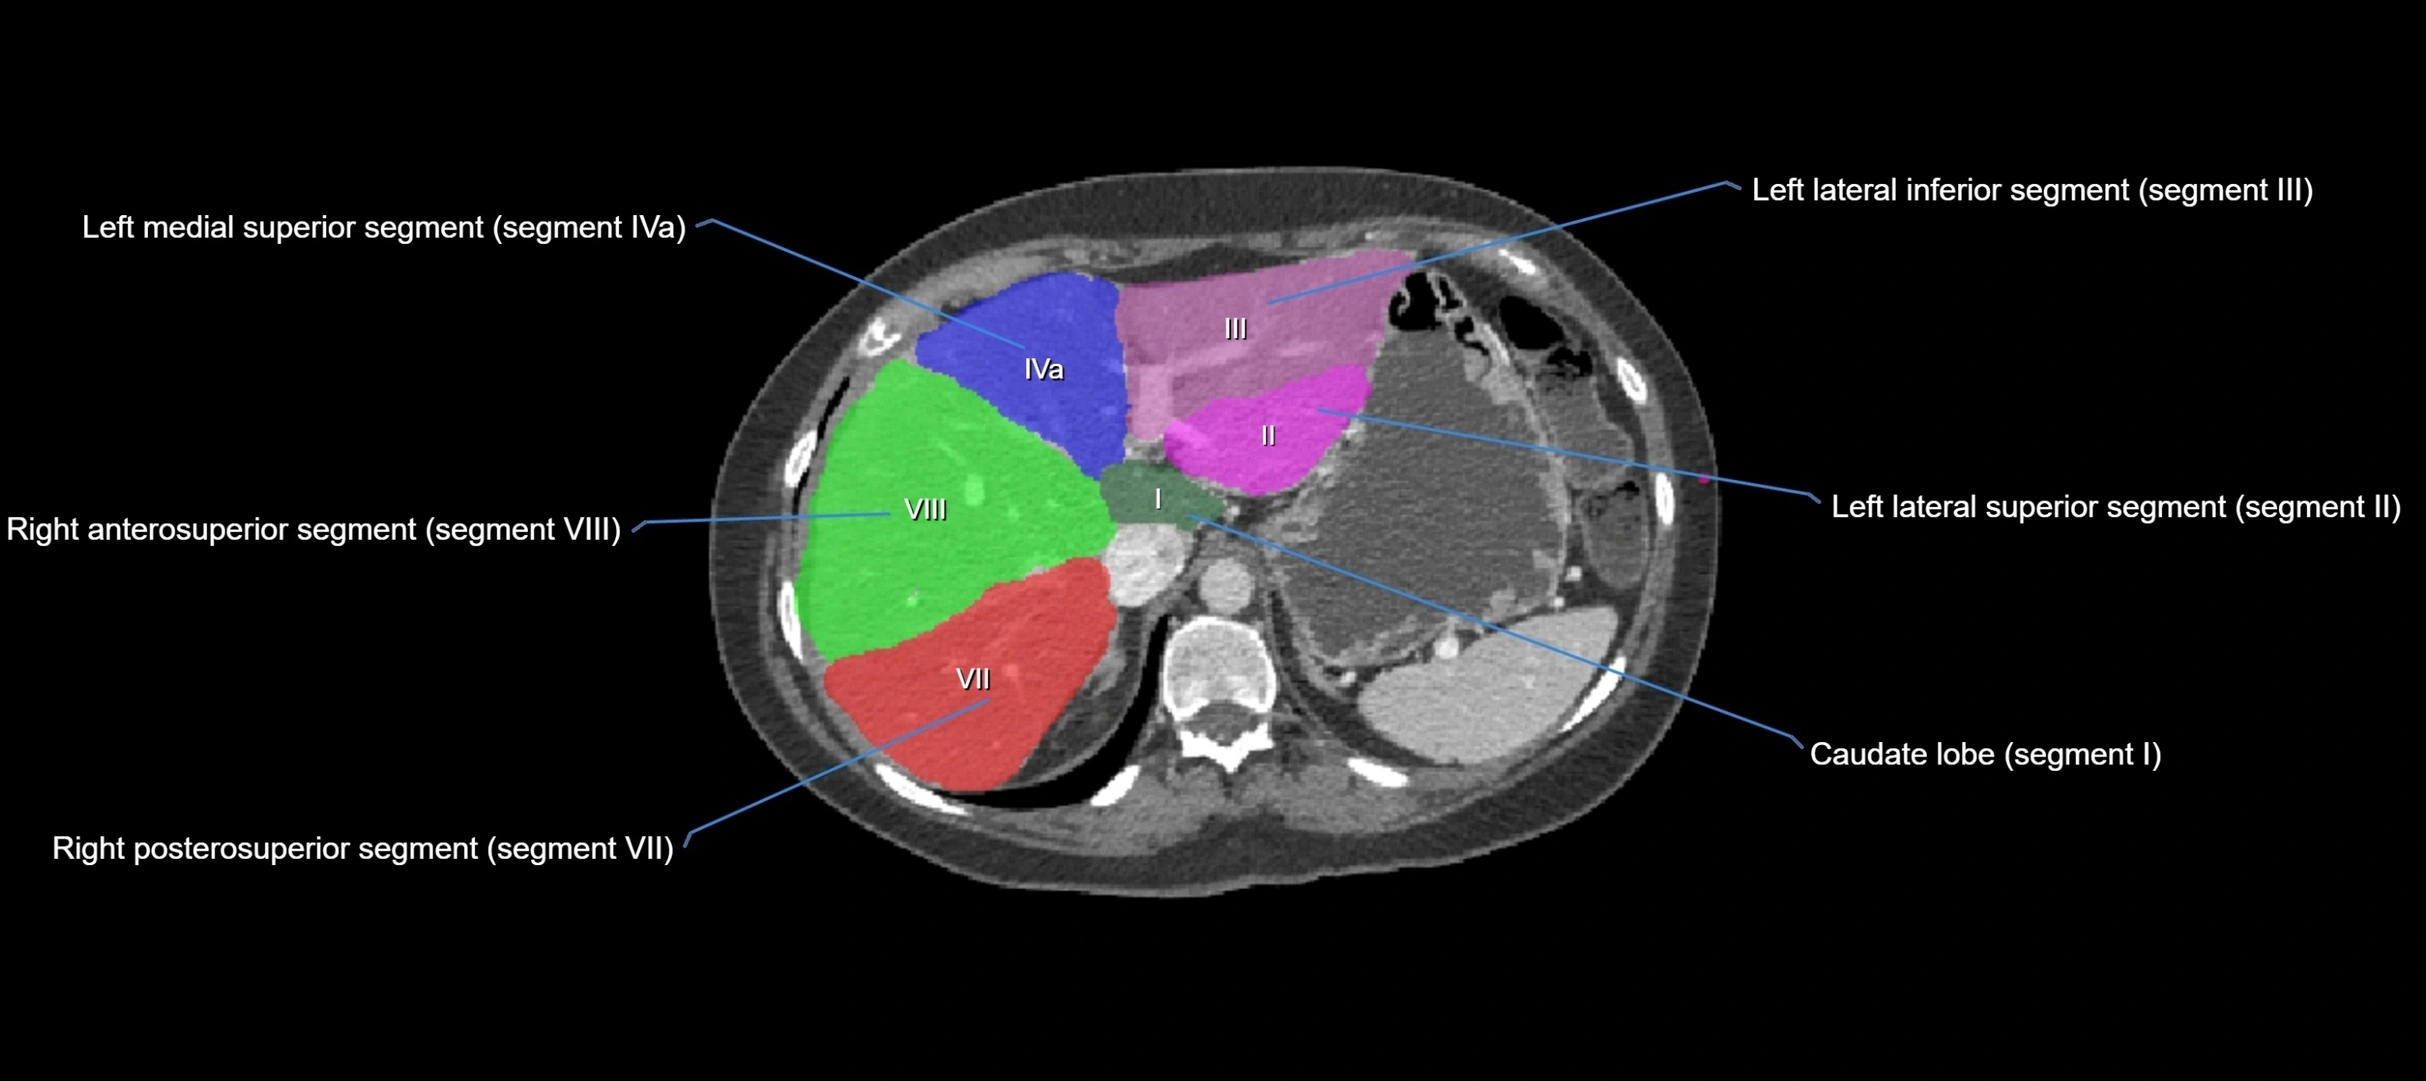

The caudate lobe of the liver is a distinct anatomical subdivision of the liver, designated as segment I in Couinaud’s classification. It lies on the posterior surface of the liver, between the fissure for the ligamentum venosum (left boundary) and the groove for the inferior vena cava (IVC) (right boundary). Superiorly, it is related to the posterior liver surface, and inferiorly it is separated from the left lobe by the porta hepatis.

The caudate lobe is unique because it receives dual portal venous and arterial inflow from both the right and left portal veins and hepatic arteries. It also has independent venous drainage directly into the IVC via multiple small hepatic veins, unlike other lobes that drain through the three main hepatic veins.

CT Image

image